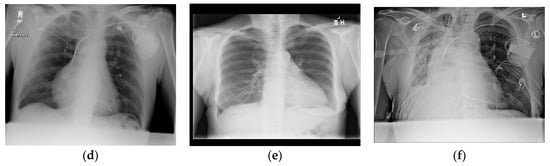

- Wang, X.; Peng, Y.; Lu, L.; Lu, Z.; Bagheri, M.; Summers, R.M. ChestX-Ray8: Hospital-scale Chest X-Ray database and benchmarks on weakly-supervised classification and localization of common thorax diseases. In Proceedings of the 2017 IEEE Conference on Computer Vision and Pattern Recognition (CVPR), Honolulu, HI, USA, 21–26 July 2017; pp. 3462–3471. [Google Scholar] [CrossRef]